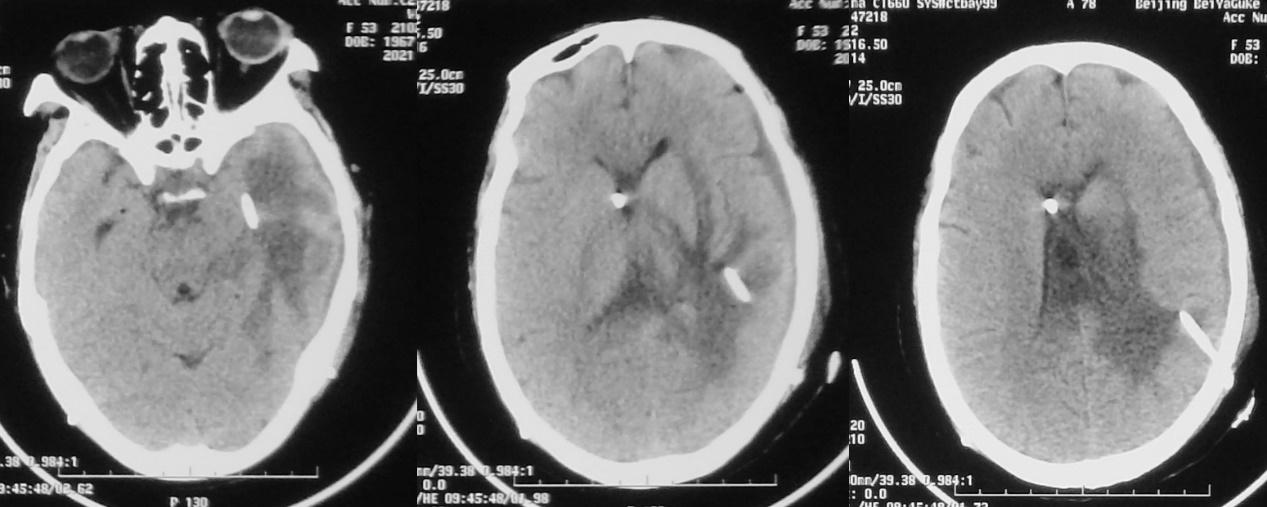

发病后21天,脑室外引流后8天,即2020年11月29日,复查头颅CT见左侧脑室较前(2020年11月22日)缩小( 图-6 ),继续抗炎及脑室外引流治疗。

图-6: 2020年11月29日头CT

脑室外引流结合抗炎治疗后第13天(2020年12月4日)和15天(2020年12月6日),患者意识仍呈嗜睡至昏睡状态,病情无明显好转,复查头颅CT见左侧丘脑病变周围水肿较前好转,但脑室仍扩张明显( 图-8、图-9 )。

图-8: 2020年12月4日头CT

图-9: 2020年12月6日头CT

患者一直呈嗜睡至昏睡状态,强刺激才能对答,仍发热,体温持续在38℃左右。于发病后29天,抗炎及脑室外引流治疗后16天,即2020年12月7日,进行了左额开颅丘脑脓肿清除术,术中经皮层造瘘口留置脑室内引流管;术后当天头CT( 图-10 )呈术后改变。

图-10: 2020年12月7日头CT

脓肿清除术后第1天,2020年12月8日,意识障碍较术前加重,呈朦胧状态,不能对答;复查头颅CT见术区少量出血,左侧脑室颞角明显扩张( 图-11 );当天紧急行左侧脑室颞角穿刺外引流术。

图-11: 2020年12月8日头CT